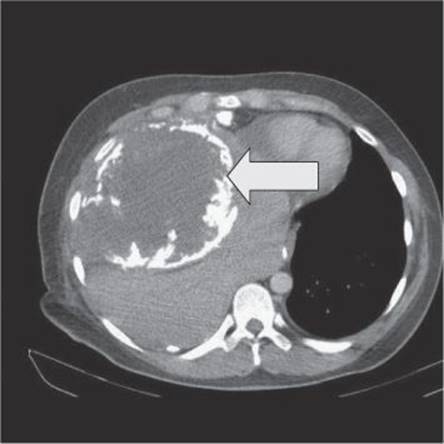

After further treatment, the patient remained well for 23 months but was found to have an abnormal chest X-ray at follow-up. CT staging is shown in Fig. 24.4.

Fig. 24.4

The CT scan (Fig. 24.4) shows an extensive lesion with calcification. In view of the large size of the recurrence there is no realistic curative treatment option. Palliative options, if the patient chooses to opt for palliative chemotherapy, could include gemcitabine with docetaxel or oral etoposide. Opting for supportive care only would also be an option if the patient chooses. Her prognosis is now severely limited due to the rapid occurrence (between 3-monthly chest X-rays) of a large tumour bulk. Palliative care services should be involved from an early stage.